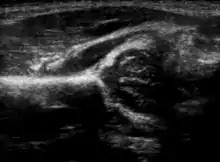

![]() | |

| Congenital dislocation of the left hip in an elderly person. Closed arrow marks the acetabulum, open arrow the femoral head. | |